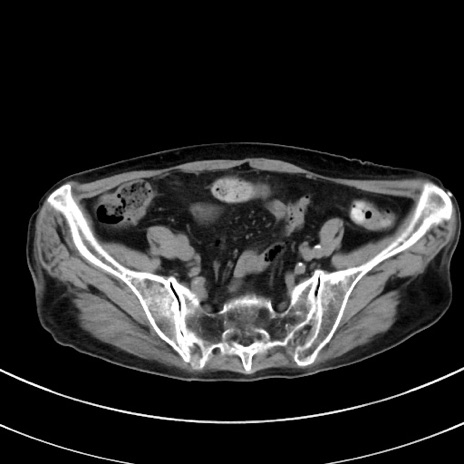

症例33(横断像)

【症例】70歳代 女性

【主訴】心窩部痛

【現病歴】延髄病変の精査・加療にて神経内科入院中。本日より心窩部痛あり。

【既往歴】虫垂炎

【身体所見】右下腹部を中心に圧痛と反跳痛あり。

【データ】WBC 10900、CRP 0.02